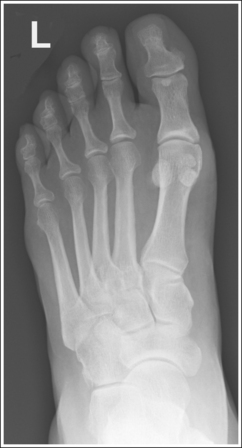

See Figure 6-12 and Box 6-5.

The foot demonstrates uniform density across the phalanges, metatarsals, and tarsals.

The foot demonstrates an AP projection. The joint space between the medial (first) and intermediate (second) cuneiforms is open, approximately 0.75 inch (2 cm) of the calcaneus is demonstrated without talar superimposition, and concavity on both sides of the first metatarsal midshaft is equal.